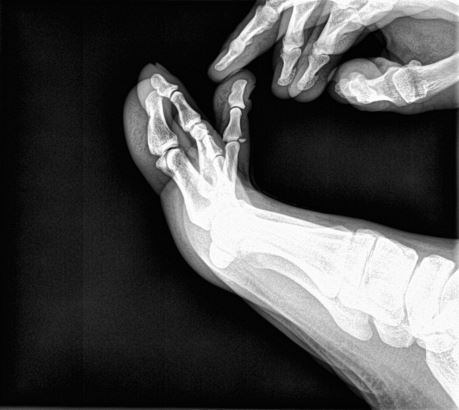

임현우원장 발가락 견열골절 이라는데 수술을 해야 할 지 고민 입니다

3월29일 운동 중 부딪혀  타박상 인 줄 알고 지내다  4월21일 인근 의원에서 사진을 찍어보니 우측 세번째 둘째 마디 견열골절 이라고 합니다 시간이 많이  지연되어 깁스는 의미가 없고 수술에 대해 전문병원과 상의해 보라고 하시네요 걸을 때 통증은 거의 없고 만지면 아픈 상태고 구부리고 펴는건 되는데 약간의 통증이 있고  4주 지난 현재도 붓기가 있고 피부색이 어두운 붉은색 입니다  사진에서 보면 뼛조각이 피부쪽으로 뽀족하게 솟아 있는데 이게 혹시 나중에도 통증을 유발 할지 걱정이네요 수술을 해야 할까요? 한다면 어떤 방법으로 진행 되는지 알고 싶습니다